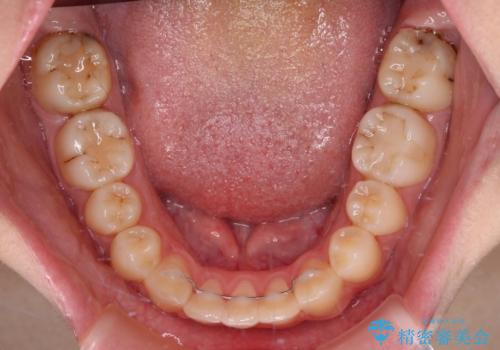

目立つ八重歯を治したい インビザラインによる矯正治療

- 目立つ八重歯を改善したいとのことで来院された患者様です。

奥歯の咬み合わせは左右とも理想的なものでしたが、下顎前歯が1本欠損しているため、上下のバランスを保つことが難しい歯列でした。

唇を閉じたときに上顎前歯が下顎の唇に乗っかる印象があったため、八重歯の後方にある小臼歯を1本抜歯することとしました。

変則的な抜歯となるため、臼歯の咬合が理想的でなくなることが懸念されますが、インビザラインにて矯正治療を行うこととしました。